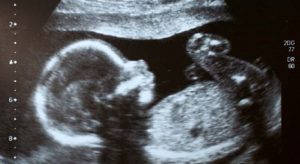

Medical checks and ultrasound examinations of the mother already showed that the developing baby’s stomach was enlarged, and doctors later confirmed the unusual condition after the child was born, the report added.

After birth, the baby underwent furter ultrasound examinations and an X-ray,and doctors had to remove two more formations from inside the baby, the report said.